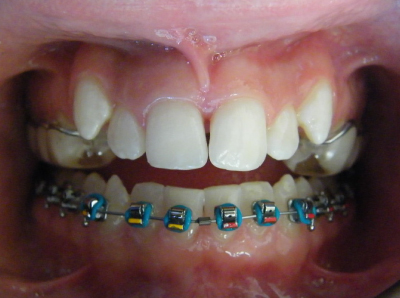

Expansion of the top jaw is done prior to the placement of upper and lower fixed braces or Invisalign aligners.

The first two sets of photos below are the before and after photos of a patient who had expansion of the upper jaw followed by upper and lower fixed braces. The third set of photos shows a patient with an expansion plate bonded to the upper teeth and lower fixed braces.